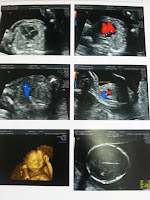

到左12w:

做左早孕期唐氏綜合症篩查

20w:

終於去照結構

醫生好好,講解好清晰

原來係長腿弟弟~

成個過程Tyrus不停郁,不過佢都好合作

要睇咩就比醫生睇^^真係乖仔